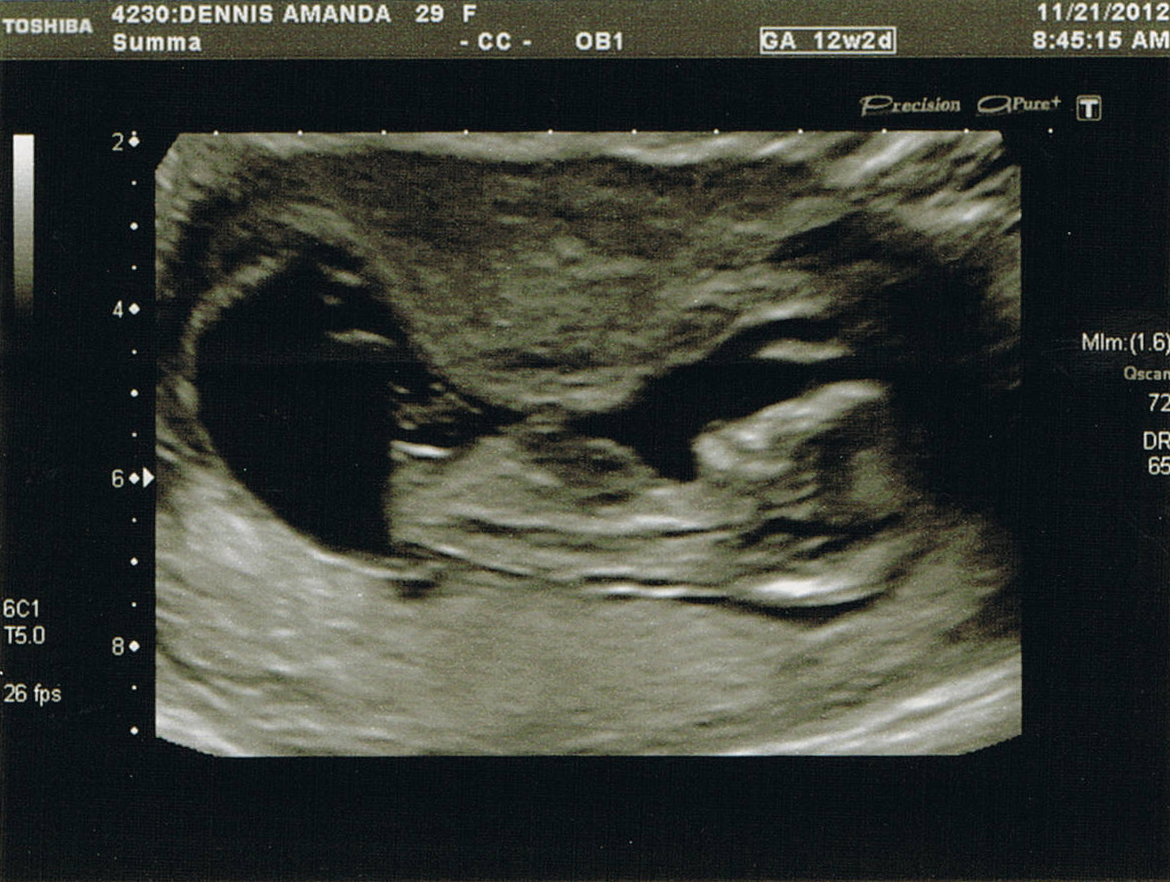

Update, 16 week ultrasound, tech was 99.9% sure it's a GIRL!!! I'm still in shock, but over the moon! Thanks everyone for all of your guesses!Attachment 7388

Im no expert but that nub looks girly to me :) x

I'd say girl from nub and skull shape

Very girly looking nub!

I'm not very good at this- but from what I've read that white line can be found on either gender's ultrasound. My eye keeps looking below that white line and I see something angled in each of the pictures. I'm going to go with boy. Fingers crossed it's your girl though!